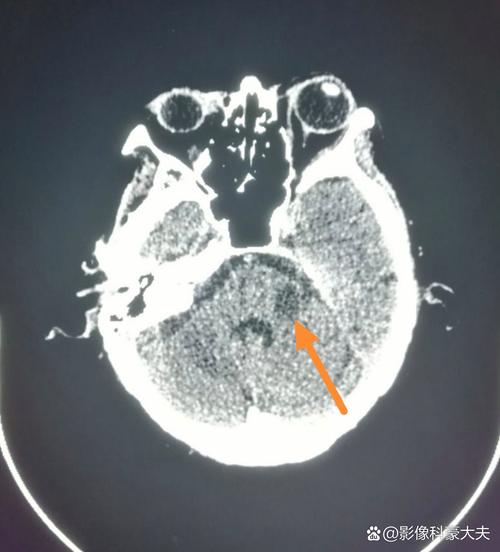

- CT表现: 因为脑组织的密度没有发生显著改变,所以高分辨率的CT在此时往往显示完全正常,无法与健康的脑组织区分开来,医生称之为“阴性CT”或“CT早期征象阴性”。

- CT表现: 大约在发病后6-24小时,CT上才可能开始看到一些细微的改变:

- 密度轻度减低: 坏死的脑组织密度比正常脑组织略低,但这种差异非常细微,经验不足的放射科医生也可能漏诊。

- 豆状核征: 在基底节区,由于对缺血更敏感,正常情况下密度较高的豆状核可能会变得模糊,与周围密度较低的苍白球界限不清。

- 大脑中动脉高密度征: 少数情况下,可以在CT上看到堵塞的大动脉(如大脑中动脉)因内有血栓而密度增高,但这并非特异性表现。

到了发病24-48小时后,CT上的低密度灶会变得非常明显和清晰,此时诊断脑梗死就非常容易了。